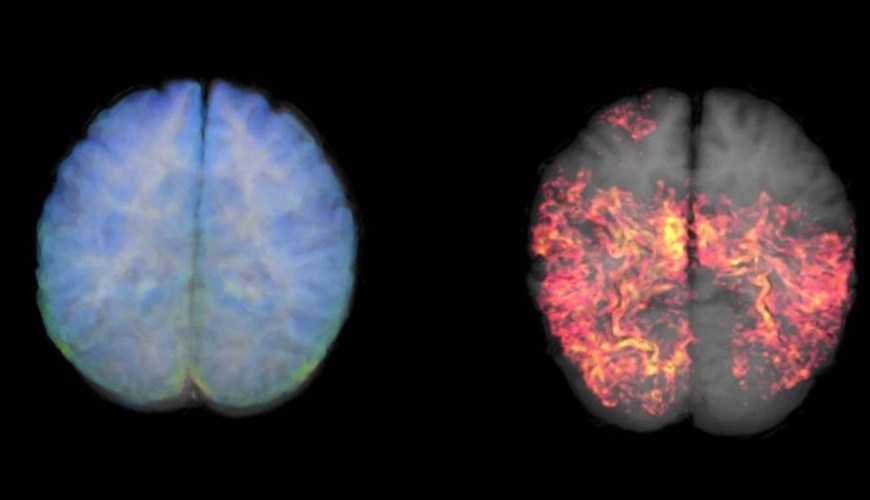

Un metaanálisis global, que evaluó a millones de pacientes, reveló que evitar el sedentarismo y respetar las horas de sueño son factores modificables clave para blindar nuestro cerebro. Frente a una enfermedad que aún no tiene cura, la ciencia confirma que la prevención más eficaz está en nuestros hábitos cotidianos.